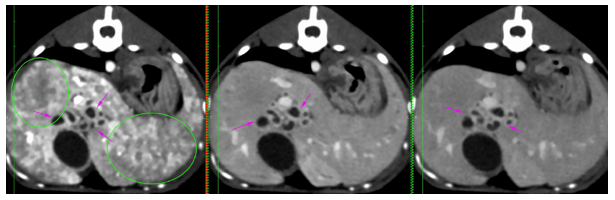

At the age of 4 months, a dual-phase (portal and delayed-venous) abdominal CT was performed to further describe the lesions and the extent of the process (SOMATON Scope CT VC40, 16-slice CT, Siemens, USA). A non-ionic iodinated contrast agent consisting of iohexol (Omnipaque™, GE Healthcare) was administered via an intravenous bolus. Post-contrast results of the examination were represented by hepatomegaly with large tubular structures, non-enhancing and hypoattenuating to the surrounding parenchyma, present throughout the liver (Figure 4A, C-red arrowhead). The tubular structures follow the approximate location of the biliary ducts with a branching pattern within the liver, close to the hepatic vasculature. (Figure 4A, B-orange arrowhead). There was difficulty encountered in identifying the gallbladder, as a result of numerous distended loops (Figure 1A-yellow arrows). A 9 mm, large, distended structure extending throughout the right limb of the pancreas to the region of the duodenal papilla was noted (Figure 4D-green arrows). The pancreatic duct was mildly distended, measuring less than 3 mm in diameter. The distended structures were filled with fluid attenuation content (10 – 20 HU) with a variably thickened wall (less than 4 mm). The hepatic changes had a marked mass effect, with right-sided displacement of the caudal vena cava noted due to the mass effect of hepatic changes. The mesenteric vasculature was relatively prominent, with many tortuous vessels present medial at the left kidney in the region of the left gastric vein and cranial mesenteric artery (Figure 4D-purple arrows). There was no evidence of a single well-defined congenital extrahepatic or intrahepatic shunt.

Figure 4 Transverse (A, B, D) and coronal (C) abdominal CT 0.75 mm slice image- Distended intrahepatic ducts causing a mass effect at the level of the cranial abdomen (red arrow) and pancreatic cyst (green arrow). A mild peritoneal effusion was noted, although this finding was unremarkable for the age of the patient.

CT scans have been performed similarly to the previous case Moderate distension of the gallbladder with hypoattenuating fluid (10 HU) has been recorded. Variable distension of the extrahepatic bile ducts( 4.7 mm) and common bile duct (2-6.5 mm) with multiple tortuous tubular structures with hypoattenuating content and thick wall on the medial aspect of the gallbladder and ventral to the portal vein (Figure 7 - pink arrows). The exact termination of the duodenal papilla was not visible, but the distal aspect of the common bile duct measures normal (< 4mm) and there is an increased contrast uptake at the level of the papilla.

Figure 7 Distended extrahepatic bile ducts with tortuous trajectory. No obvious cause of obstruction has been seen on the CT scan. Moderate intraabdominal lymphadenopathy (hepatic - 1.1 cm, green arrows), jejunal and ileocaecocolic most severely, up to 8 mm, left/caudal colic 6-7 mm, have been seen with the rest of the abdominal and pelvic lymph nodes mildly enlarged.

Other findings have been represented by a diffusely enlarged liver with rounded edges, extending caudally from the coastal arch. Multiple small contrast-enhancing vessels with marked, but diffusely heterogeneous contrast uptake throughout the liver in the arterial phase have been seen (green circles) – Figure 8. The proportional size of the aorta, caudal vena cava, and portal vein at the level of the porta hepatica was relatively normal.

Figure 8 Multiple contrast-enhancing hepatic vessels. Distension on the bile ducts with marked thickened walls. No anomalous connections of the portal system have been seen.